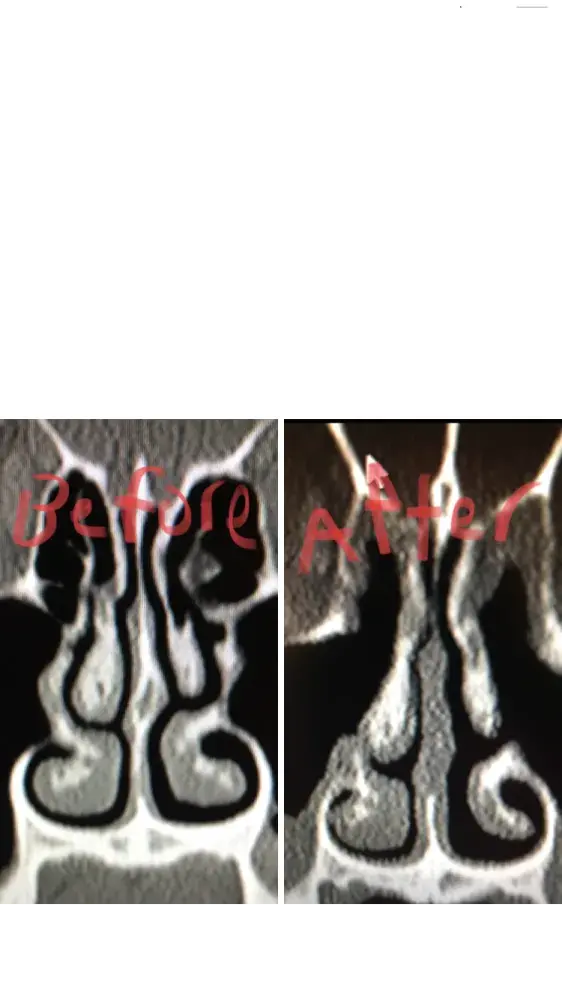

For people reading this, I have included x-ray images of the inside of my nose, before and after my surgery with him. As you can see from these images, my nasal airway was equally open on both sides, before surgery, and the septoplasty didn't need to be done. By performing it, he severely narrowed the right side of my nasal airway.

He performed this unnecessary surgery to collect that additional insurance money. There is no other explanation for this. Furthermore, when I later contacted him, and told him that my breathing was worse, and I suspected it was a problem with my septum, he told me that he wouldn't be able to perform the revision septoplasty (make the septum way it was before). Therefore, not only is he greedy, by performing unnecessary surgeries, but he is incompetent, for not being able to fix his mistakes.

Dr Raviv performed two surgeries on me: endoscopic sinus surgery (where they widen the sinus passages), and septoplasty (where they straighten the septum). The septoplasty, however was completely unnecessary, and severely narrowed the right side of my nasal airway. For people reading this, I have included x-ray images of my sinuses, before and after my surgery with Dr. Raviv. As you can see from the surgery, my airway was much more open, and equal on both sides, before my surgery with him.